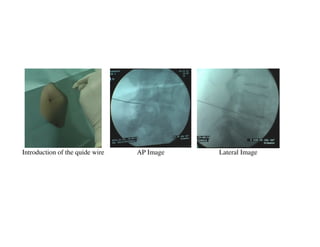

TECHNIC OF COBLATION

Position and marking of the entry point and direction of the disk of interest

Local anesthesia                                Incision of the skin

Introduction of the quide wire   AP Image   Lateral Image